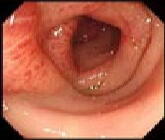

大腸黒皮症 (70才女性) |

「黒皮症」は便秘のために、緩下剤を使用されている方々によく見られる所見です。

健康な方の腸の内側はきれいなピンク色しているのですが、長期間(数年)に下剤(センナ、アロエ等)を服用し続けますと右図のように、褐色から甚だしい場合には太陽の照らない腸の中なのに日焼けしたごとく「真っ黒」になります。メラニン様色素が腸壁に沈着するために、このような変化が起こります。 緩下剤を中止しますと、約6ヶ月後には、幸いにも元のピンク色に戻ります。

大腸黒皮症ポリ−プはおもしろいことに色素は沈着しません(左)。

中央に小ポリ−プが見られますより高度になると、真黒になり、snake skin (蛇の皮)と称されるほどの色素沈着を来す(右)。